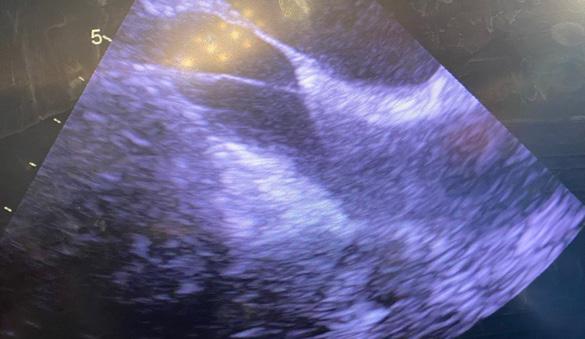

Pacientul este plasat în decubit dorsal cu umărul drept ușor ridicat; este anestezi at și intubat cu sondă dublu lumen care să permită ventilația selectivă pulmonară. Se introduce o sondă de ecocardiografie tran sesofagiană (ETE) cu ajutorul căreia se confirmă diagnosticul preoperator și me canismul patologiei mitrale, se ghidează canularea periferică pentru circulație ex tracorporală (CEC) și se evaluează funcția cadiacă și calitatea gestului asupra VMi. Pacientul este rotat 30 grade către stânga, efectuându-se o toracotomie antero-la terală de 5-7 cm în al IV-lea spațiu inter costal. Rotirea pacientului către stânga nu este obligatorie, multe centre renunțând la această abordare, din cauză că inima se îndepărtează de toracele drept. În schimb, este important ca brațul drept să fie flectat la 120 grade și în ușoară abducție, pentru a se îndepărta de viitoarea incizie (Fig.1,2).

zitive de etanșeizare vasculară tip Proglide. ETE confirmă prezența ghidului în lumenul aortei descendente toracice (Fig.6), preve nind cea mai de temut complicație a canu lării periferice: disecția retrogradă de aortă.

Abia după ce se confirmă localizarea ghidului, se avansează canula arterială femurală. După canularea arterială se continuă cu cea venoasă. Indiferent dacă se utilizează o canulă “single-stage” sau “dual-stage”, ghidul trebuie avansat și ve rificat în atriul drept (AD) până la nivelul venei cave superioare (VCS) (Fig.7).

Se avansează apoi cu canula venoasă; în cazul canulării VCI se verifică ecogra fic și tactil (dacă se poate) prezența canu lei la joncțiunea VCI cu AD (Fig.8).